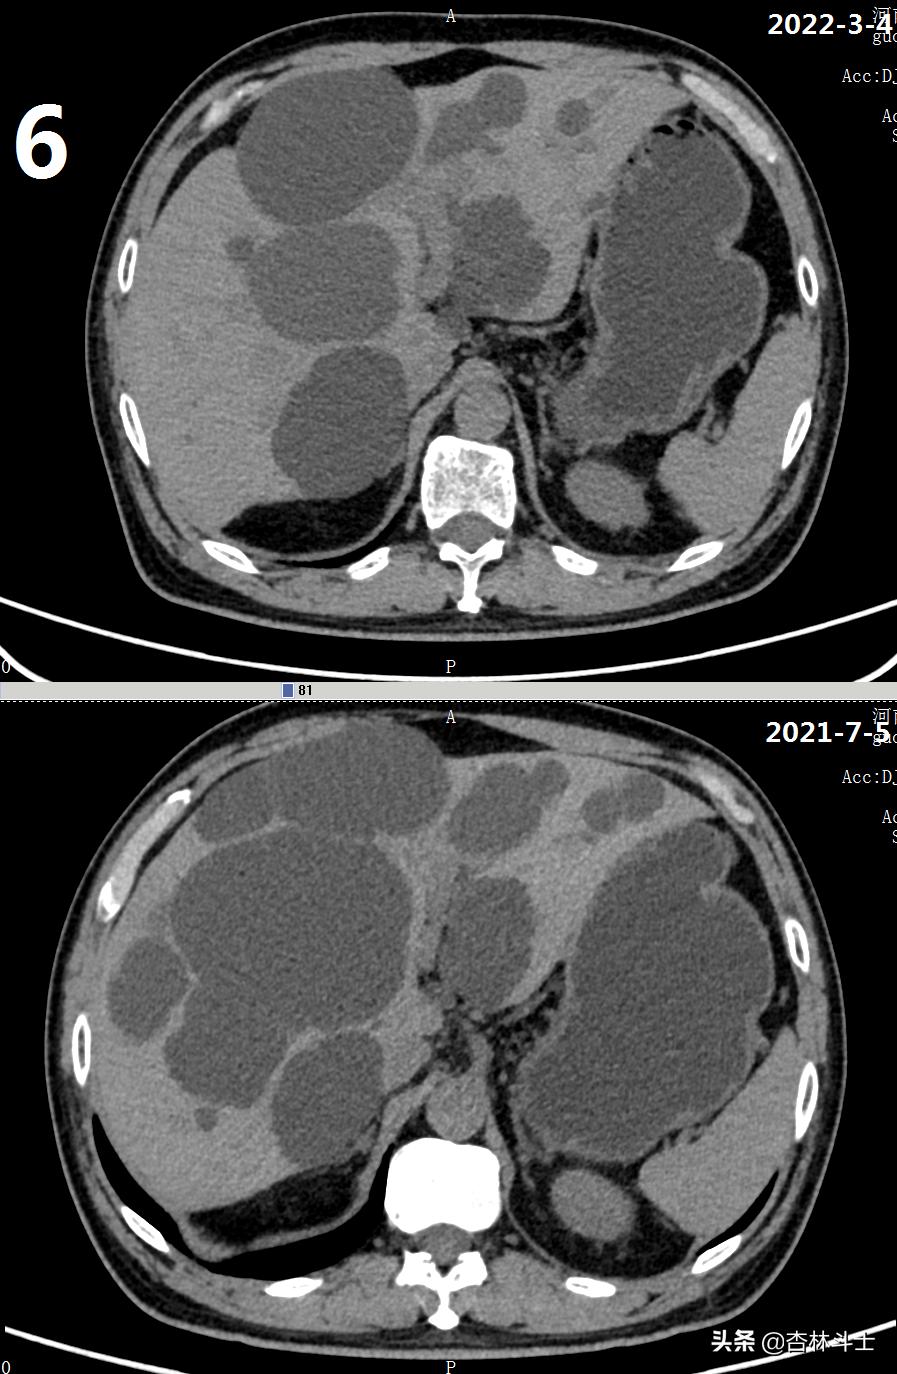

64岁退休银行职员,腹胀5年,加重2月,第二次入住我院消化内科。下图1-6为本次复查上腹部CT与2021-7-5肝囊肿经皮肝穿刺抽吸无水酒精硬化术前的对比图。

可明显看出,肝内囊肿较前减少,肝实质所占体积明显增加。